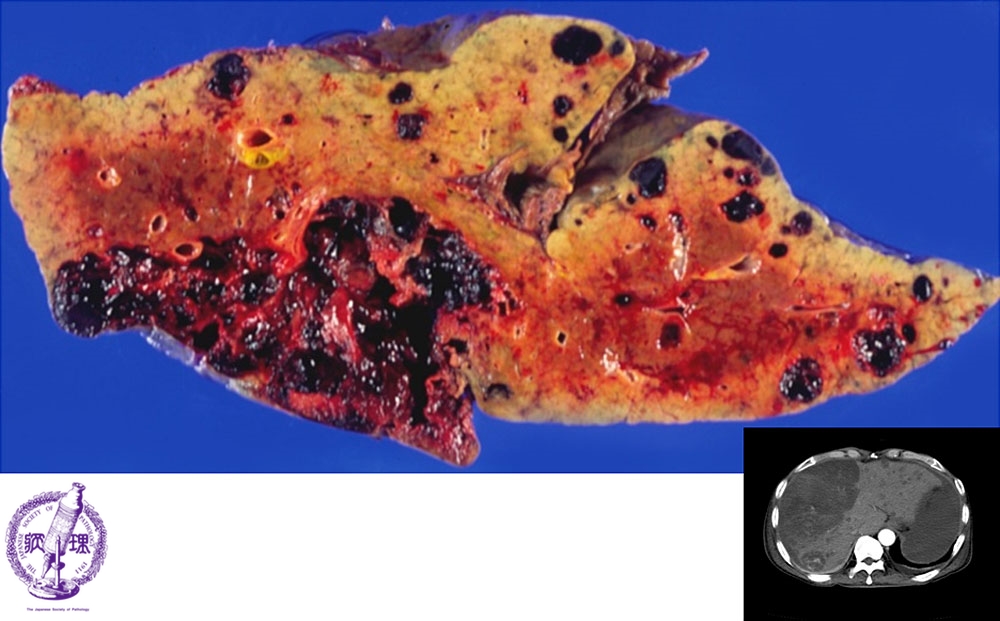

- ★(14)Angiosarcoma of the liver

Macroscopic image: There is sponge-like tumor which contains reddish-brown thrombus (yellow arrows) and demonstrates an expansive, obscure boundary.Right lower: In the CT image, the low-density area (black color) corresponds to tumor (red arrow).